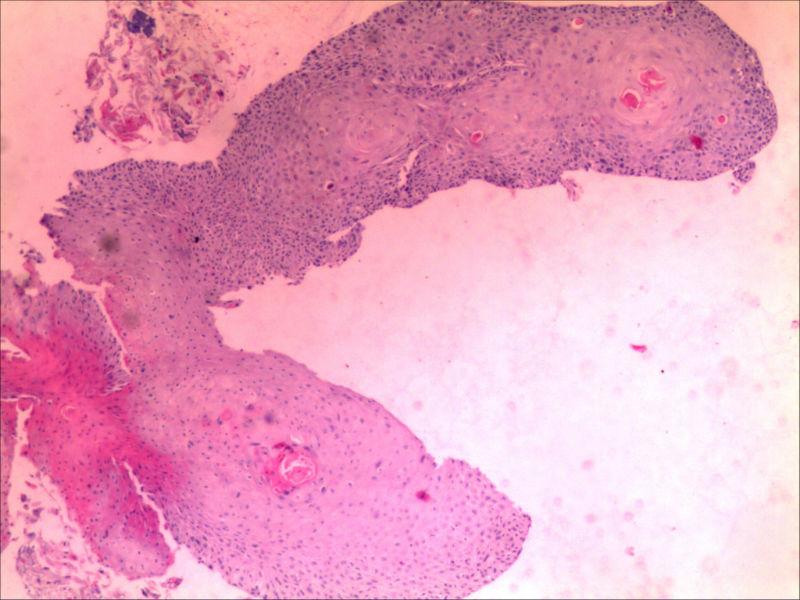

食管活检男64岁食管粗糙

• 食管活检男64岁食管粗糙图1

图1

高级别上皮内瘤变,取材表浅,不排除高分化鳞癌,请结合临床建议必要时再取活检

同意,本例仅出现食管黏膜粗糙,如果没有较大肿块或溃疡,也有可能就是个高度上皮内瘤变或早期食管癌。因此可做超声内镜,如果可能,做大黏膜切除治疗。